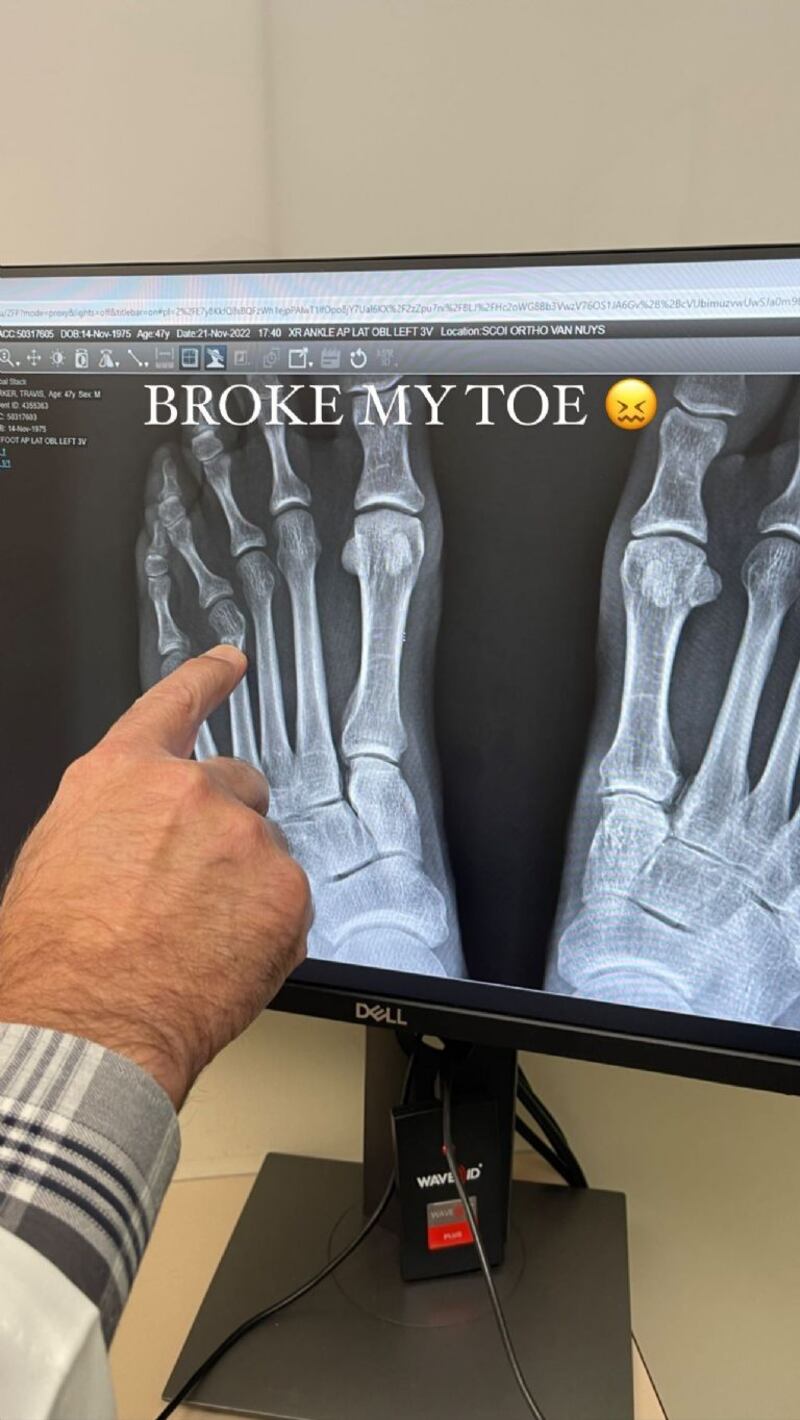

A través de sus redes sociales, el esposo de Kourtney Kardashian (43) escribió: “Me rompí un maldito dedo” y acompañó su mensaje con la fotografía de una radiografía en la cual puede verse su pie y el dedo afectado. En otra instantánea se aprecia al músico en compañía de los doctores, quienes le ponen la bota para inmovilizar su extremidad y esto permita su pronta recuperación.